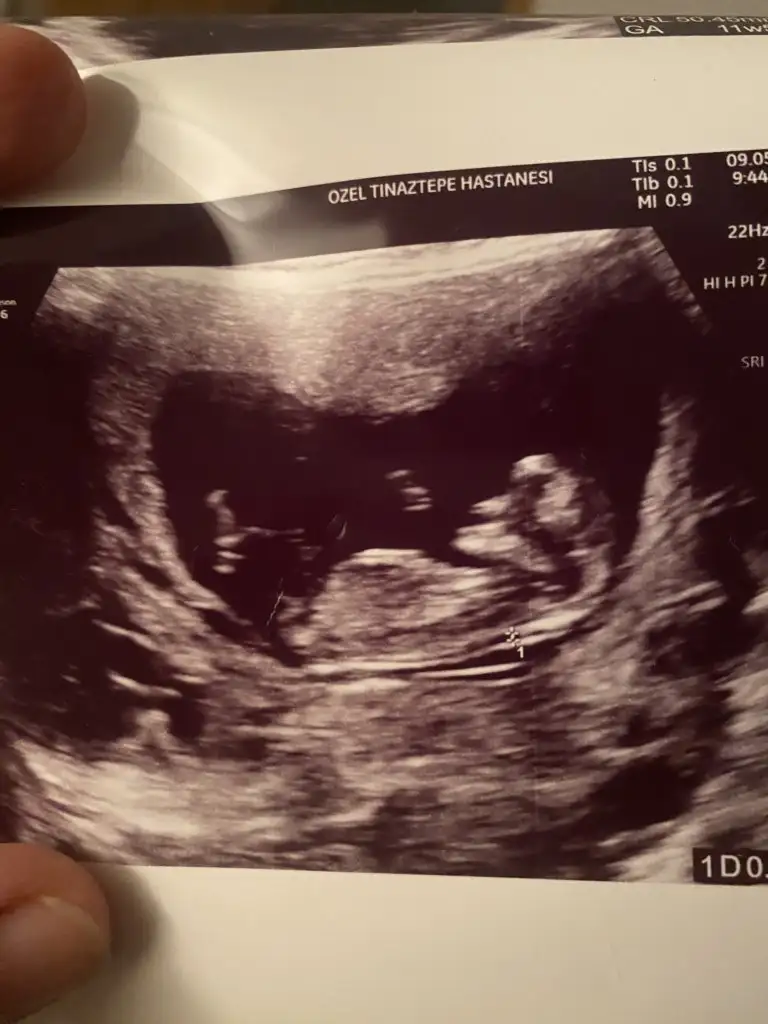

Canım kız gibi11+2 karından ultrason cinsiyet yorumu yapabilir mısınız ?

Teşekkür ederimCanım kız gibi

Benimkine de bakarmisiz lutfen atmistim resimleriCanım kız gibi